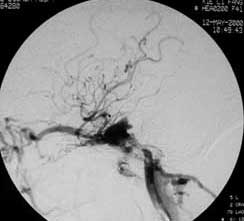

四.硬脑膜动静脉瘘(AVF)

----硬脑膜AVF是一种极复杂的颅内血管病,其分型方法可根据静脉引流的方式为:硬膜窦型、皮层静脉型、硬脑膜窦至皮 层静脉型、硬膜下静脉湖型、脊髓静脉型。也可以根据瘘口发生部分为:海绵窦区,横窦乙状窦区、窦汇区、上矢状窦 区、颅底区。栓塞治疗方法须根据分型而定,原则上是以永久性栓塞剂闭塞瘘口。单纯行瘘口孤立术,既创伤大,又难以 彻底解决问题,一支支供血动脉的栓塞,则此起彼伏,诸多侧支循环,十分棘手。通过对引流静脉血液动力学分析,针对 静脉窦的"竞争性血流",可以采取静脉窦闭塞的方法,从根本上解决多发性瘘口,在这方面一系列的血液动力学、影像解 剖学以及胚胎学的研究对治疗难治性脑膜动静脉瘘均有重要意义。